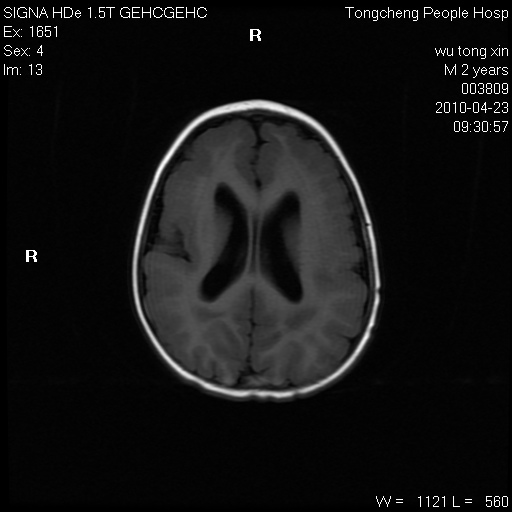

以下是引用赵物学在2010-4-25 12:43:00的发言:[br]巨脑回[br]侧脑室后角低密度影考虑hie或肾上腺脑白质营养不良?[br][br][本贴已被 赵物学 于 2010-4-25 12:51:28 修改过]

以下是引用gaoxiao在2010-4-25 16:54:00的发言:[br]巨脑回畸形。脑白质髓鞘化不良

以下是引用pujunzhi在2010-4-25 21:35:00的发言:[br]考虑 1双侧大脑皮质发育不良 2轻度脑积水 3双侧脑室后角旁片状长t1长t2信号,需继续观察,因为正常小儿此处脑白质的髓鞘化时间可以延迟到4-6岁,才显示正常。